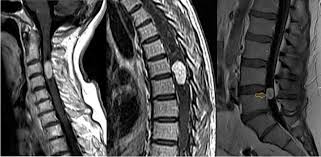

Mielopatia

Es una compresión de la médula espinal que puede causar debilidad, alteraciones en la marcha o pérdida de fuerza en las extremidades.

Tumores

Algunas lesiones tumorales pueden afectar la columna vertebral y provocar dolor persistente o síntomas neurológicos que requieren evaluación médica.